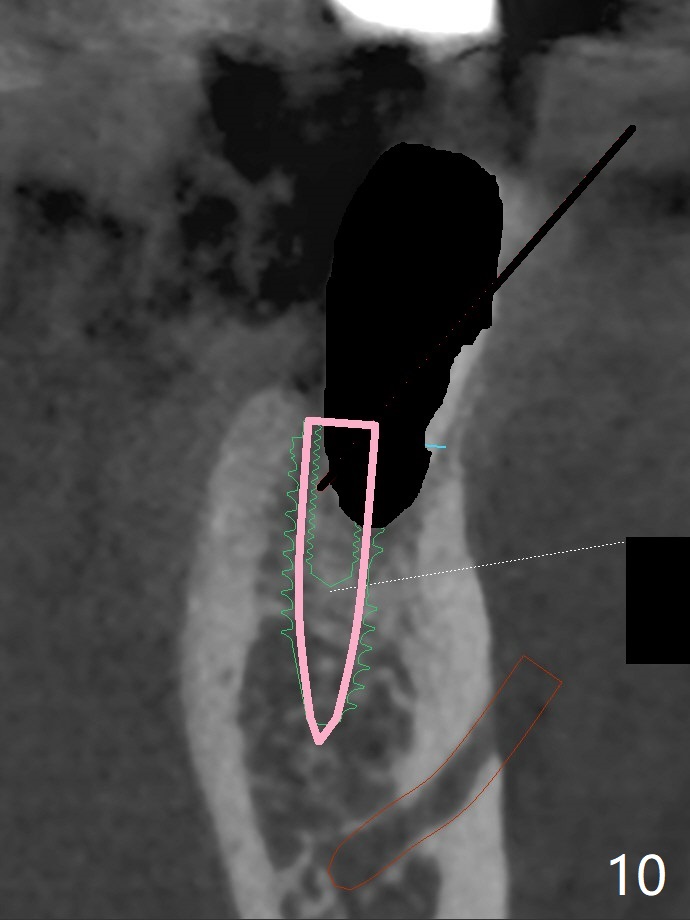

Re-analysis of preop CT reveals extensive bone loss around #18 (Fig.1 (lingual view)). Blood is withdrawn for sticky bone. After implant placement (Fig.2), sticky bone is placed at #18 (Fig.3 red dashed line (yellow: superior border of the Inferior Alveolar Canal)). PRF membrane and an immediate provisional FPD (#18-20) further keep the bone graft in place for healing. Four months postop, the patient reports difficulty in mastication on the left and requests extraction of the tooth #20 for implant (Fig.4). The implant will be placed lingually, while socket shield will be performed buccally (Fig.5 S) to keep bone graft in place. The implant at #19 is equicrestal (Fig.6); the one at #18 is apparently supracrestal buccally (Fig.7). Since there is a lot of scattering from nearby crowns, the implant at #20 will be placed free hand. To overcome the thick dense lingual plate (Fig.8 L), osteotomy is initiated (Fig.9 red line) in the middle of the lingual wall of the extraction socket (black area) on the top of the socket shield (S). After the last drill (3.5x11.5 mm, Fig.10 pink) and before 4x11.5 mm implant, use Lindamann bur to remove the coronal portion of the lingual plate (Fig.11 red line) to prevent implant buccal deviation.